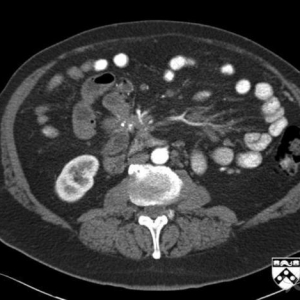

病例学习:胰腺炎影像诊断技巧

病史:女性,73岁,既往有原发性高血压和Ⅱ型糖尿病,因发热和腹部剧痛来急诊室就诊。该患者在急诊室观察时休克昏厥。该患者被送入重症监护室,并给予高剂量抗生素静脉滴注。之后患者病情稳定,未进行手术治疗。两个 ...